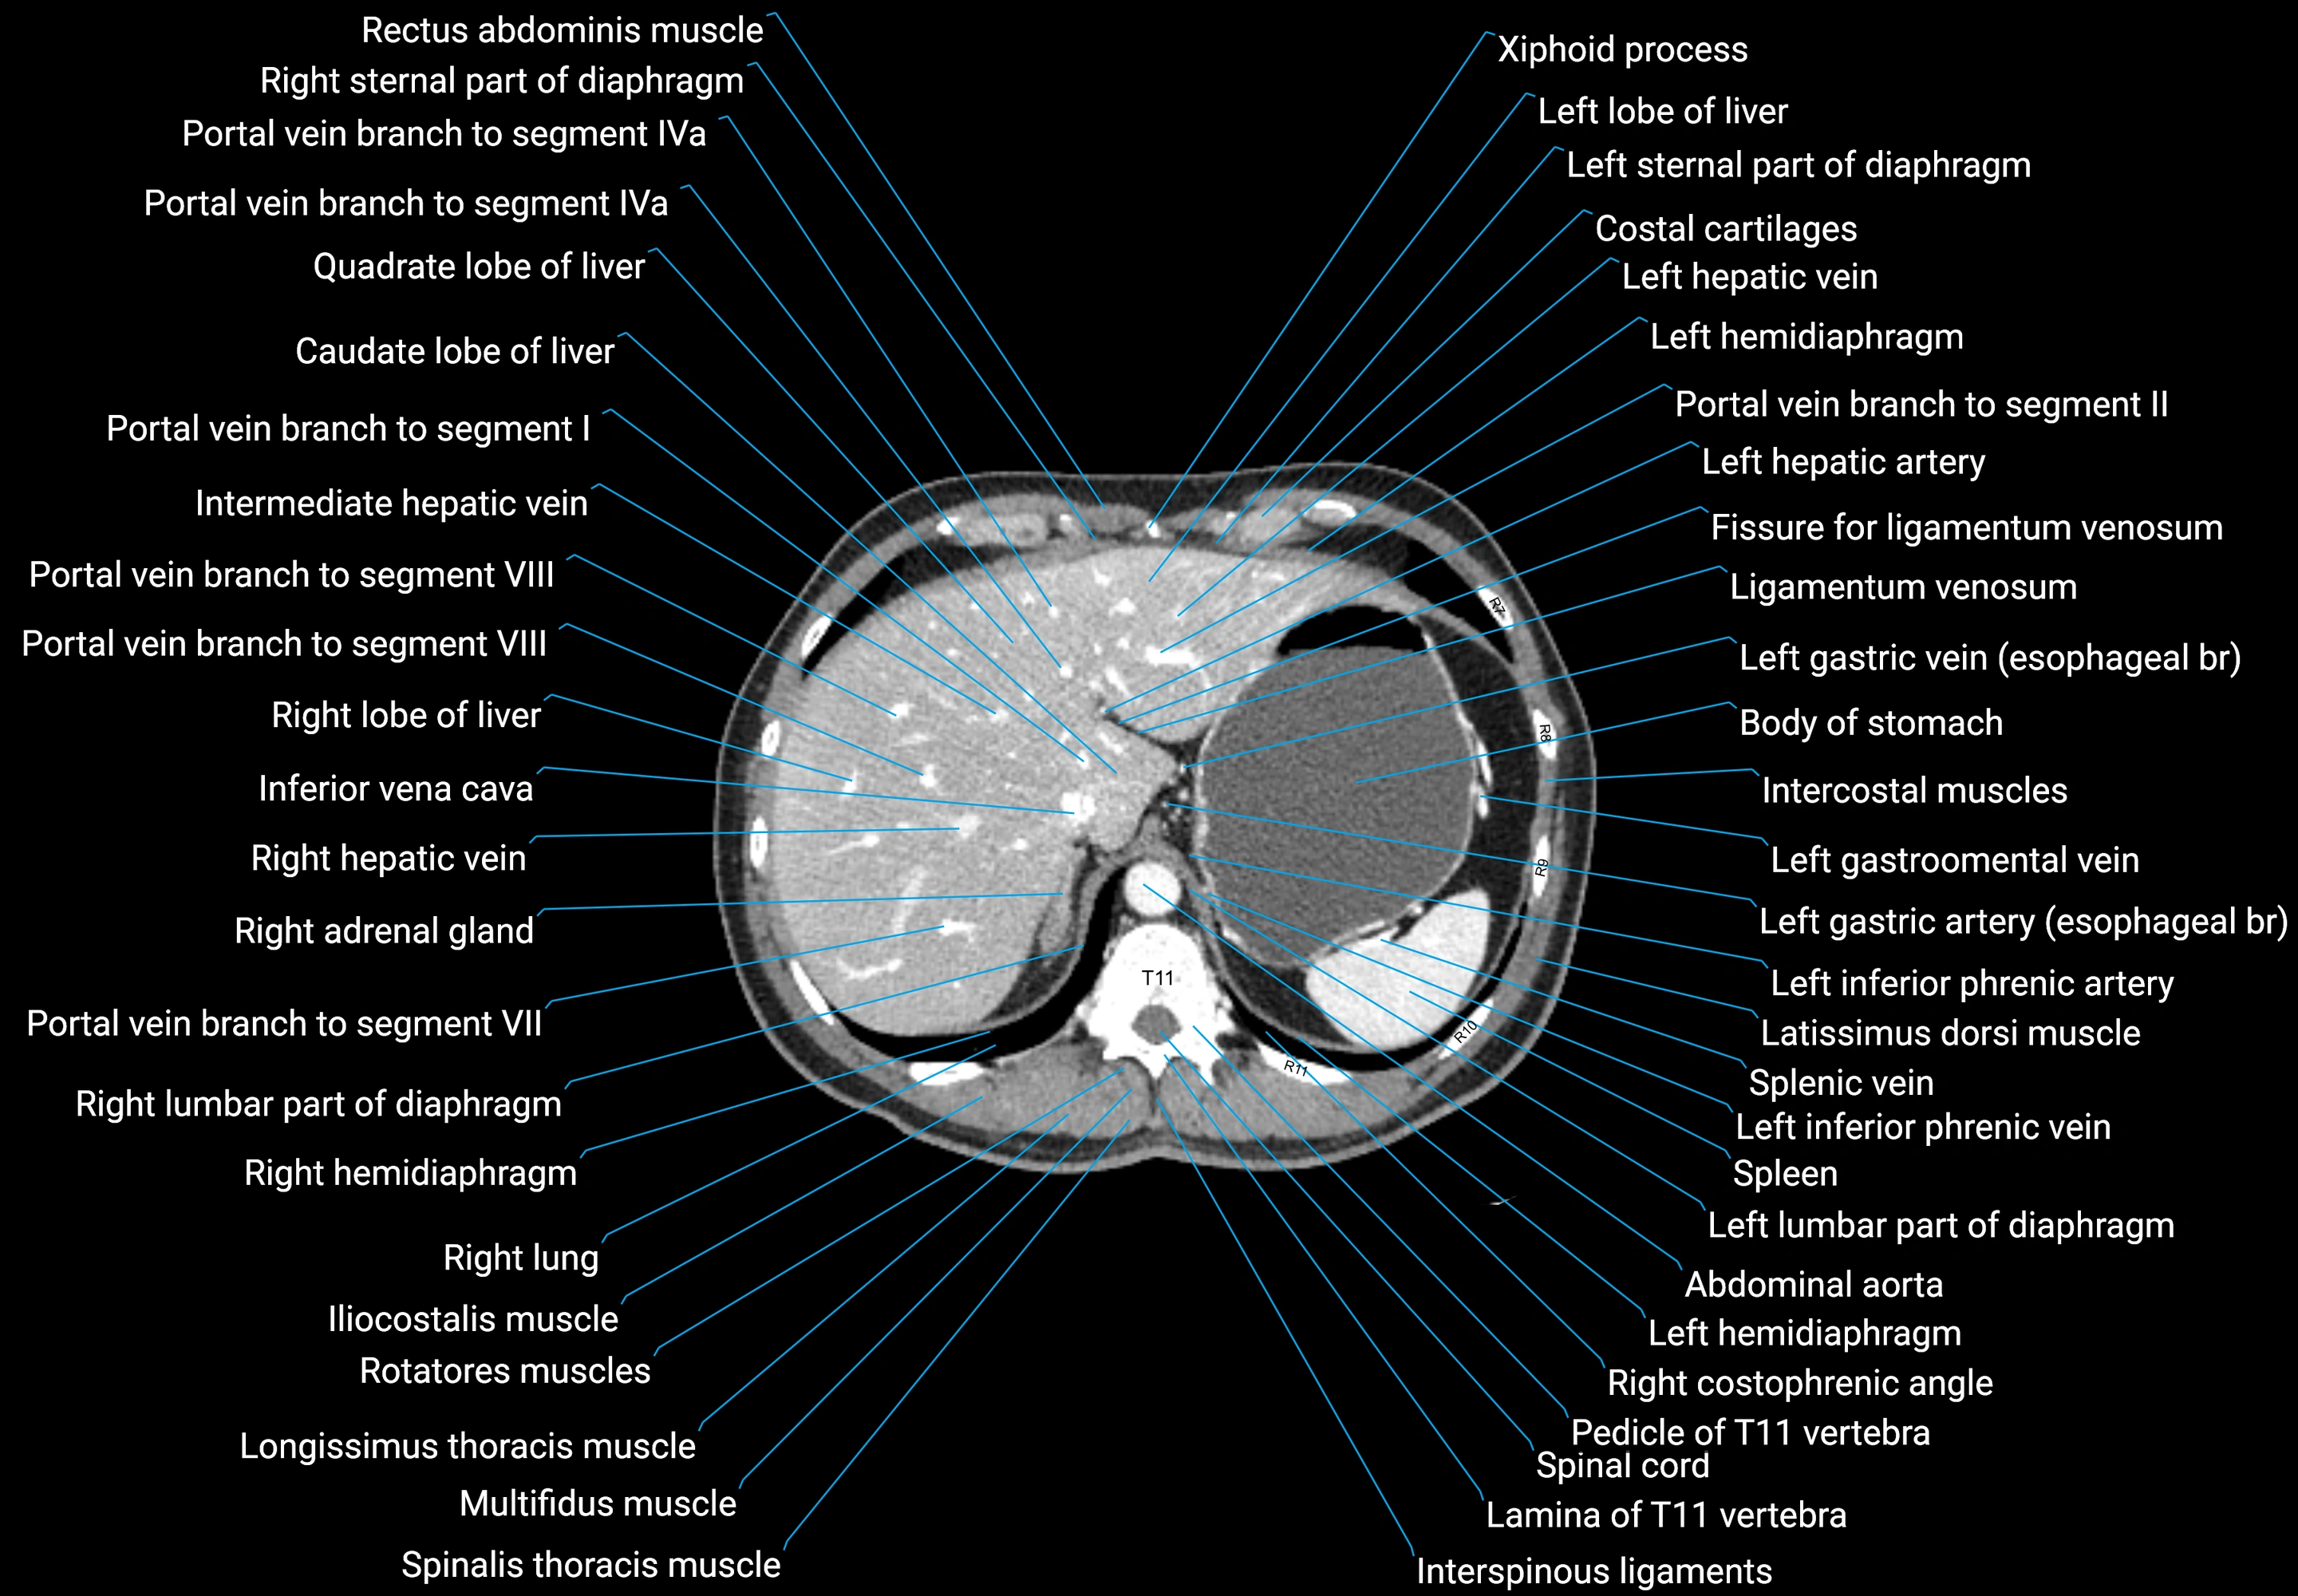

CT images